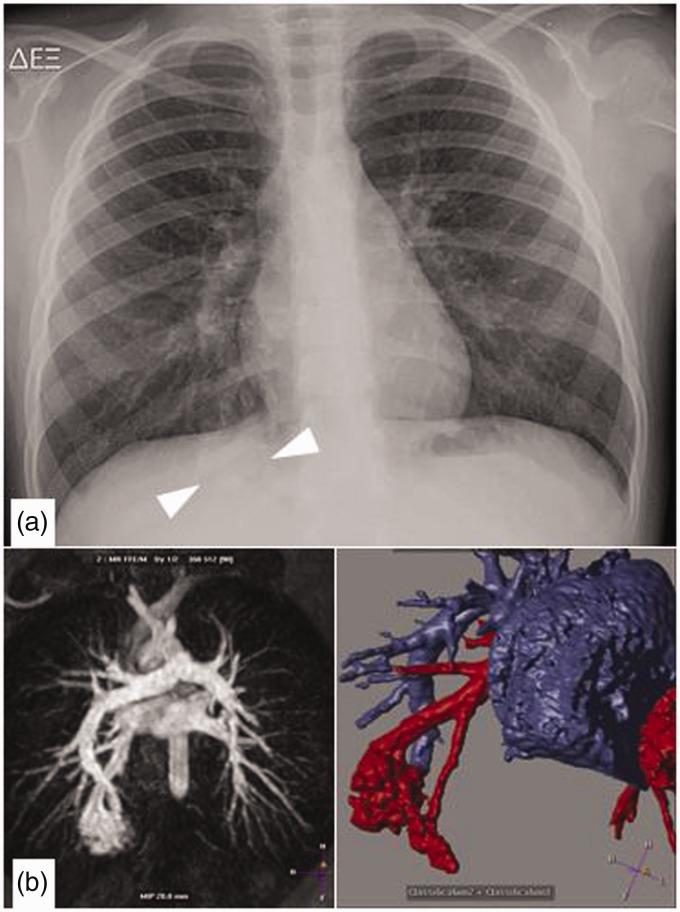

The purpose of this current pictorial review is to define the solitary round pulmonary lesion (SRPL), to familiarize with its prevalence in the pediatric population, and, moreover, to educate radiologists on its vast differential diagnosis and imaging manifestations. Furthermore, by highlighting valuable clues, it intends to assist radiologists efficiently partake in its diagnosis, work-up, and follow-up in order to narrow down the differential diagnosis by working alongside the clinician and combining clinical information, lab results, and radiological findings.

本次影像综述的目的是明确孤立性圆形肺病变(SRPL),使其在儿科人群中的患病率,此外,使放射科医生熟悉其广泛的鉴别诊断和影像学表现。此外,通过强调有价值的线索,旨在帮助放射科医生有效地参与其诊断、检查和随访,以便通过与临床医生合作并结合临床信息、实验室结果和影像学发现来缩小鉴别诊断范围。